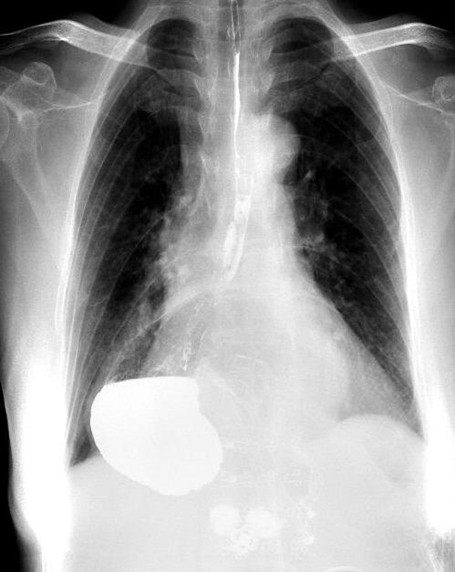

術前胃“游走”到胸腔。重慶市人民醫院供圖

人民網重慶8月20日電 近日,年近7旬的王婆婆(化名)稍進食即感覺胸部及上腹部脹悶,稍活動就感覺氣短。這種情況嚴重困擾了王婆婆,甚至以為自己得了重病。王婆婆在家人的陪同下到中國科學院大學重慶醫院(重慶市人民醫院)就醫。

接診的胸外科副主任醫師馬洪飚經過詳細詢問及完善相關檢查,發現王婆婆所患的疾病叫“食管裂孔疝”,由此造成了胃的“離家出走”,有一部分跑到了胸腔里面,才會出現上述不適。

在完善術前準備后,胸外科主任馬錚帶領馬洪飚副主任醫師、張兵兵主治醫師通過微創手術不僅將王婆婆游走到胸腔的胃還納到了腹腔,還修補了拳頭大小的食管裂孔,以防止胃再次離家出走。手術后王婆婆恢復順利,術前的不適癥狀消失,目前已經順利出院。

馬洪飚醫生介紹:人的胸腔和腹腔通過膈。ㄒ粔K完整而扁平的肌肉)分隔開來,食管的下端通過膈肌上的天然裂孔進入腹腔同胃相連,這個天然的裂孔就叫食管裂孔,它的大小只能容納食管(大拇指大。┩ㄟ^,然而有些人因為先天因素(如膈肌纖維發育不良)或后天因素(肥胖、長期咳嗽、便秘等引起腹腔內壓力升高)導致食管裂孔明顯擴大,食管下端、胃、腸等腹腔內臟器就會通過擴大的食管裂孔疝入胸腔,從而使病人出現進食易飽、反酸、燒心、胸骨后疼痛、吞咽困難、活動后氣短等不適,甚至出現消化道出血、穿孔等并發癥,嚴重時可危及生命。(陳琦、張勤)